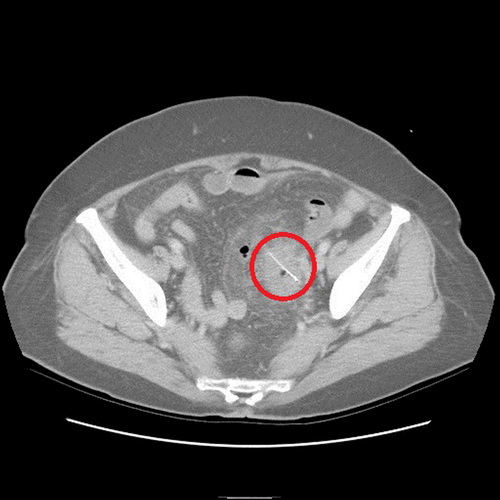

没想到过了2天,老奶奶又来看诊,医师便为她安排住院检查,经计算机断层检查,发现老奶奶乙状结肠部份竟然有根2.5公分的鱼刺,且鱼刺已经穿破肠道,导致横膈膜下方有气体出现,经外科医师协助开刀,终于顺利帮老奶奶解决腹部不适的问题。